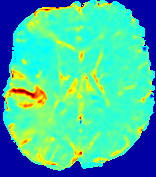

Slice #1Slice #2Slice #3Slice #4Slice #5Slice #6Dgtsuperscript𝐷gtD^{\text{gt}}Refer to captionRefer to captionRefer to captionRefer to captionRefer to captionRefer to caption(a)Refer to captionRefer to captionRefer to captionRefer to captionRefer to captionRefer to caption(b)Refer to captionRefer to captionRefer to captionRefer to captionRefer to captionRefer to caption(c)Refer to captionRefer to captionRefer to captionRefer to captionRefer to captionRefer to caption(d)Refer to captionRefer to captionRefer to captionRefer to captionRefer to captionRefer to caption(e)Refer to captionRefer to captionRefer to captionRefer to captionRefer to captionRefer to caption(f)Refer to captionRefer to captionRefer to captionRefer to captionRefer to captionRefer to captionRefer to caption000.060.060.060.120.120.120.180.180.180.240.240.240.300.300.30(mm2/s)𝑚superscript𝑚2𝑠(mm^{2}/s)

Figure 13: PIANO effectiveness and robustness testing: diffusion imaging via diffusion. Top row shows Dgtsuperscript𝐷gtD^{\text{gt}} used for simulating the ground truth pure diffusion. (a)-(f) refer to the results for D𝐷D estimated from the ground truth pure diffusion image time-series where Rician noise at levels 0%, 2%, 4%, 6%, 8%, 10% was added respectively.

Similarly, starting from the same initial condition C0superscript𝐶0C^{0} as in the ‘Advection Imaging’ experiment for each patient, we simulate concentration time-series {Cti(Ω)|i=0, 1,, 40}conditional-setsuperscript𝐶subscript𝑡𝑖Ω𝑖0140\{C^{t_{i}}\in\mathbb{R}(\Omega)|i=0,\,1,\,\ldots,\,40\} via a diffusion PDE, where we define the ground truth diffusivity D:=Dgtassign𝐷superscript𝐷gtD:=D^{\text{gt}} via the ADC map of the ISLES 2017 training set (ADC values are scaled by 0.000010.000010.00001 to ensure numerical stability):

Note this is likely not a spatially representative ground-truth for perfusion imaging, as it measures different effects from diffusion imaging. However, we still use it as a quasi-realistic pattern of diffusivity in the brain. We also added 2%, 4%, 6%, 8%, 10% levels of Rician noise to obtain simulations of ‘Diffusion Imaging’. The estimated Destsuperscript𝐷estD^{\text{est}} given concentrations of all noise levels for one patient are shown in Fig. 13, PIANO estimation results for all patients are summarized in Fig. 11 (b). Again, PIANO demonstrates its capability to recover the underlying diffusion field. In Fig. 13, when the noise level is increasing, some noisy patterns indeed appear in the associated Destsuperscript𝐷estD^{\text{est}}. Note that the ground truth diffusivity applied in this simulation experiment is about ten times larger than the diffusivity estimated in reality (Fig. 3, Fig. 4).